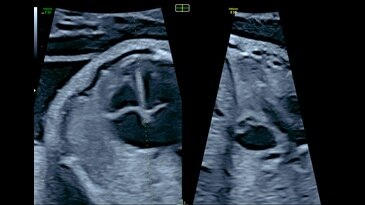

𝘧𝘦𝘵𝘢𝘭HQ

Инновационная технология Voluson для углубленной оценки сократительной

функции сердца плода. Позволяет на основе измерений в стандартных сечениях проводить детальную оценку размера и формы сердца, а также спекл-трекинг. Программное обеспечение fetalHQ включает расширенный протокол измерений, содержащий как стандартные показатели z-значений, так и процентильный расчет для каждого измерения сердца плода.

Сократимость сердца плода, представленная с помощью fetalHQ